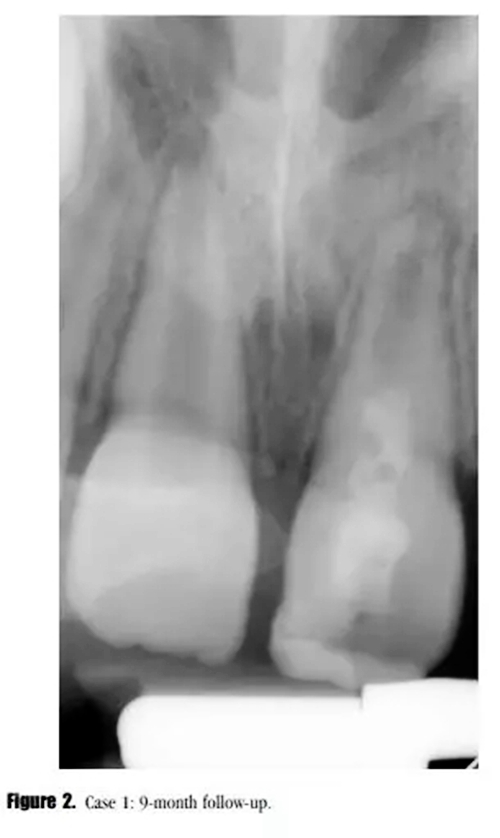

在3,6,9個(gè)月的隨后跟蹤隨訪中,患者完全沒有癥狀。與鄰牙和對(duì)側(cè)牙對(duì)比,21的叩診、捫診以及牙周袋深度都在正常范圍內(nèi)。對(duì)于牙髓溫度測(cè)試沒有反應(yīng)。影像學(xué)評(píng)估顯示,根尖區(qū)低密度透射影像范圍減小,牙根發(fā)育為I型(按照Chueh等人的研究)(圖2),